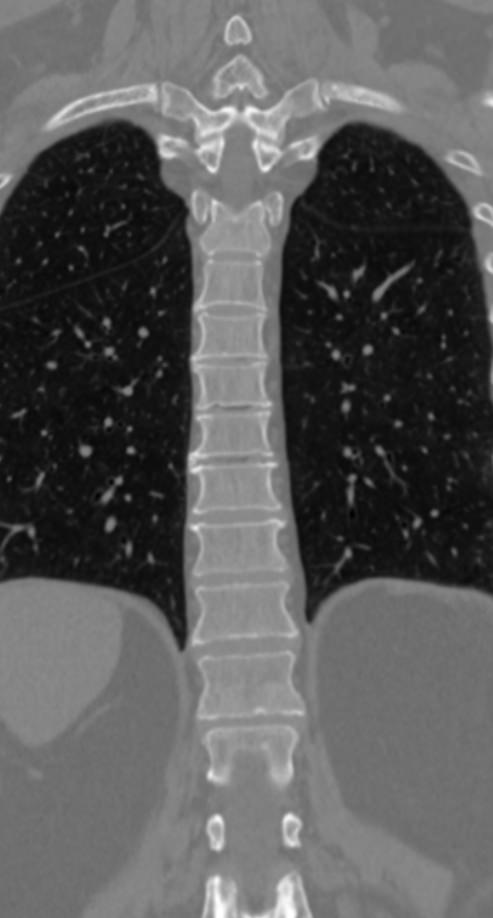

Для диагностики даже незначительных патологических изменений в различных отделах позвоночника, особенно в случае распространенного поражения, применяется один из современных наиболее информативных методов обследования – мультиспиральная компьютерная томография всего позвоночника. Методика основана на использовании проникающей способности рентгеновских лучей через органы и ткани человека и позволяет получить подробное изображение всех структур позвоночного столба. В комплексное обследование входит исследование шейного, грудного, пояснично-крестцового отделов позвоночника и копчика.

В медицинских центрах «Доступная медицина» сканирование всего позвоночника выполняется на новейших мультиспиральных компьютерных томографах последнего поколения TOSHIBA AQUILION в различных модификациях. Особенностью данных аппаратов является их способность проводить от 64 до 128 тончайших срезов одномоментно с минимальной толщиной от 0,5 мм.

Увеличенное количество высокочувствительных детекторов, которыми оснащены томографы, позволяет получать послойные снимки высокого качества с большой скоростью. Эта особенность данных аппаратов обеспечивает быстроту выполнения сканирования. При этом пациент получает минимальную дозу облучения, что имеет важное значение, особенно при такой обширной зоне исследования, как позвоночный столб.